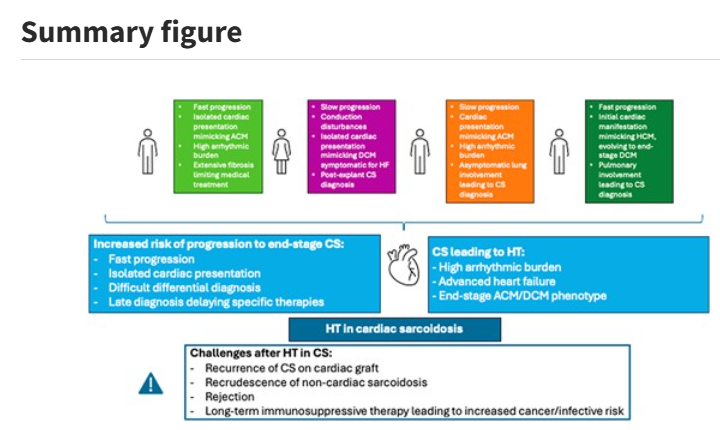

End-stage heart failure and heart transplant in cardiac sarcoidosis: a case series ow.ly/Ns1F50VSmzU #EHJCaseReports Philipp Sommer Tee Joo YEO Aaysha Cader Boldizsar Kovacs Erik Rafflenbeul A.Nazmi Calik Obayda Azizy Sara Moscatelli EHJCaseReports Editor-in-Chief #CardioX #EPeeps